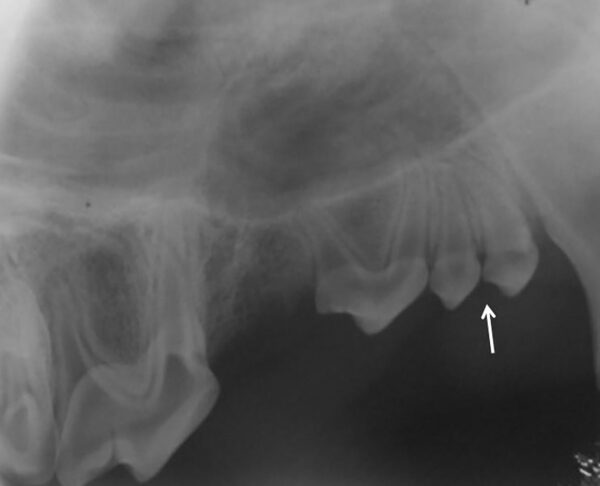

Para el diagnóstico de la EP, además de realizar un examen periodontal a través del sondaje debemos apoyarnos en la radiografía, ya que nos proporciona información acerca de la cantidad de pérdida ósea existente, así como del patrón que sigue esta pérdida (horizontal y/o vertical). En dientes multirradiculares, podemos servirnos de la furca para evaluar la pérdida de hueso, ya que aparecen áreas radiolúcidas bajo la bifurcación radicular a medida que se produce la destrucción ósea.

De acuerdo a esta pérdida del hueso alveolar detectada a nivel radiológico, clasificaremos la EP en cuatro grados:

- Grado 1 (PD1): sin pérdida ósea.

- Grado 2 (PD2): pérdida del soporte óseo menor al 25 % (imagen 7).

- Grado 3 (PD3): pérdida del soporte óseo de un 25-50 % (imagen 8).

- Grado 4 (PD4): pérdida del soporte óseo mayor de un 50 % (imagen 9).

Además de permitirnos evaluar el grado de enfermedad periodontal, también hace posible seleccionar el mejor tratamiento en función de su patología y las posibles complicaciones, como las fracturas mandibulares iatrogénicas en perros de talla pequeña con enfermedad periodontal PD4 (imágenes 10 y 11).